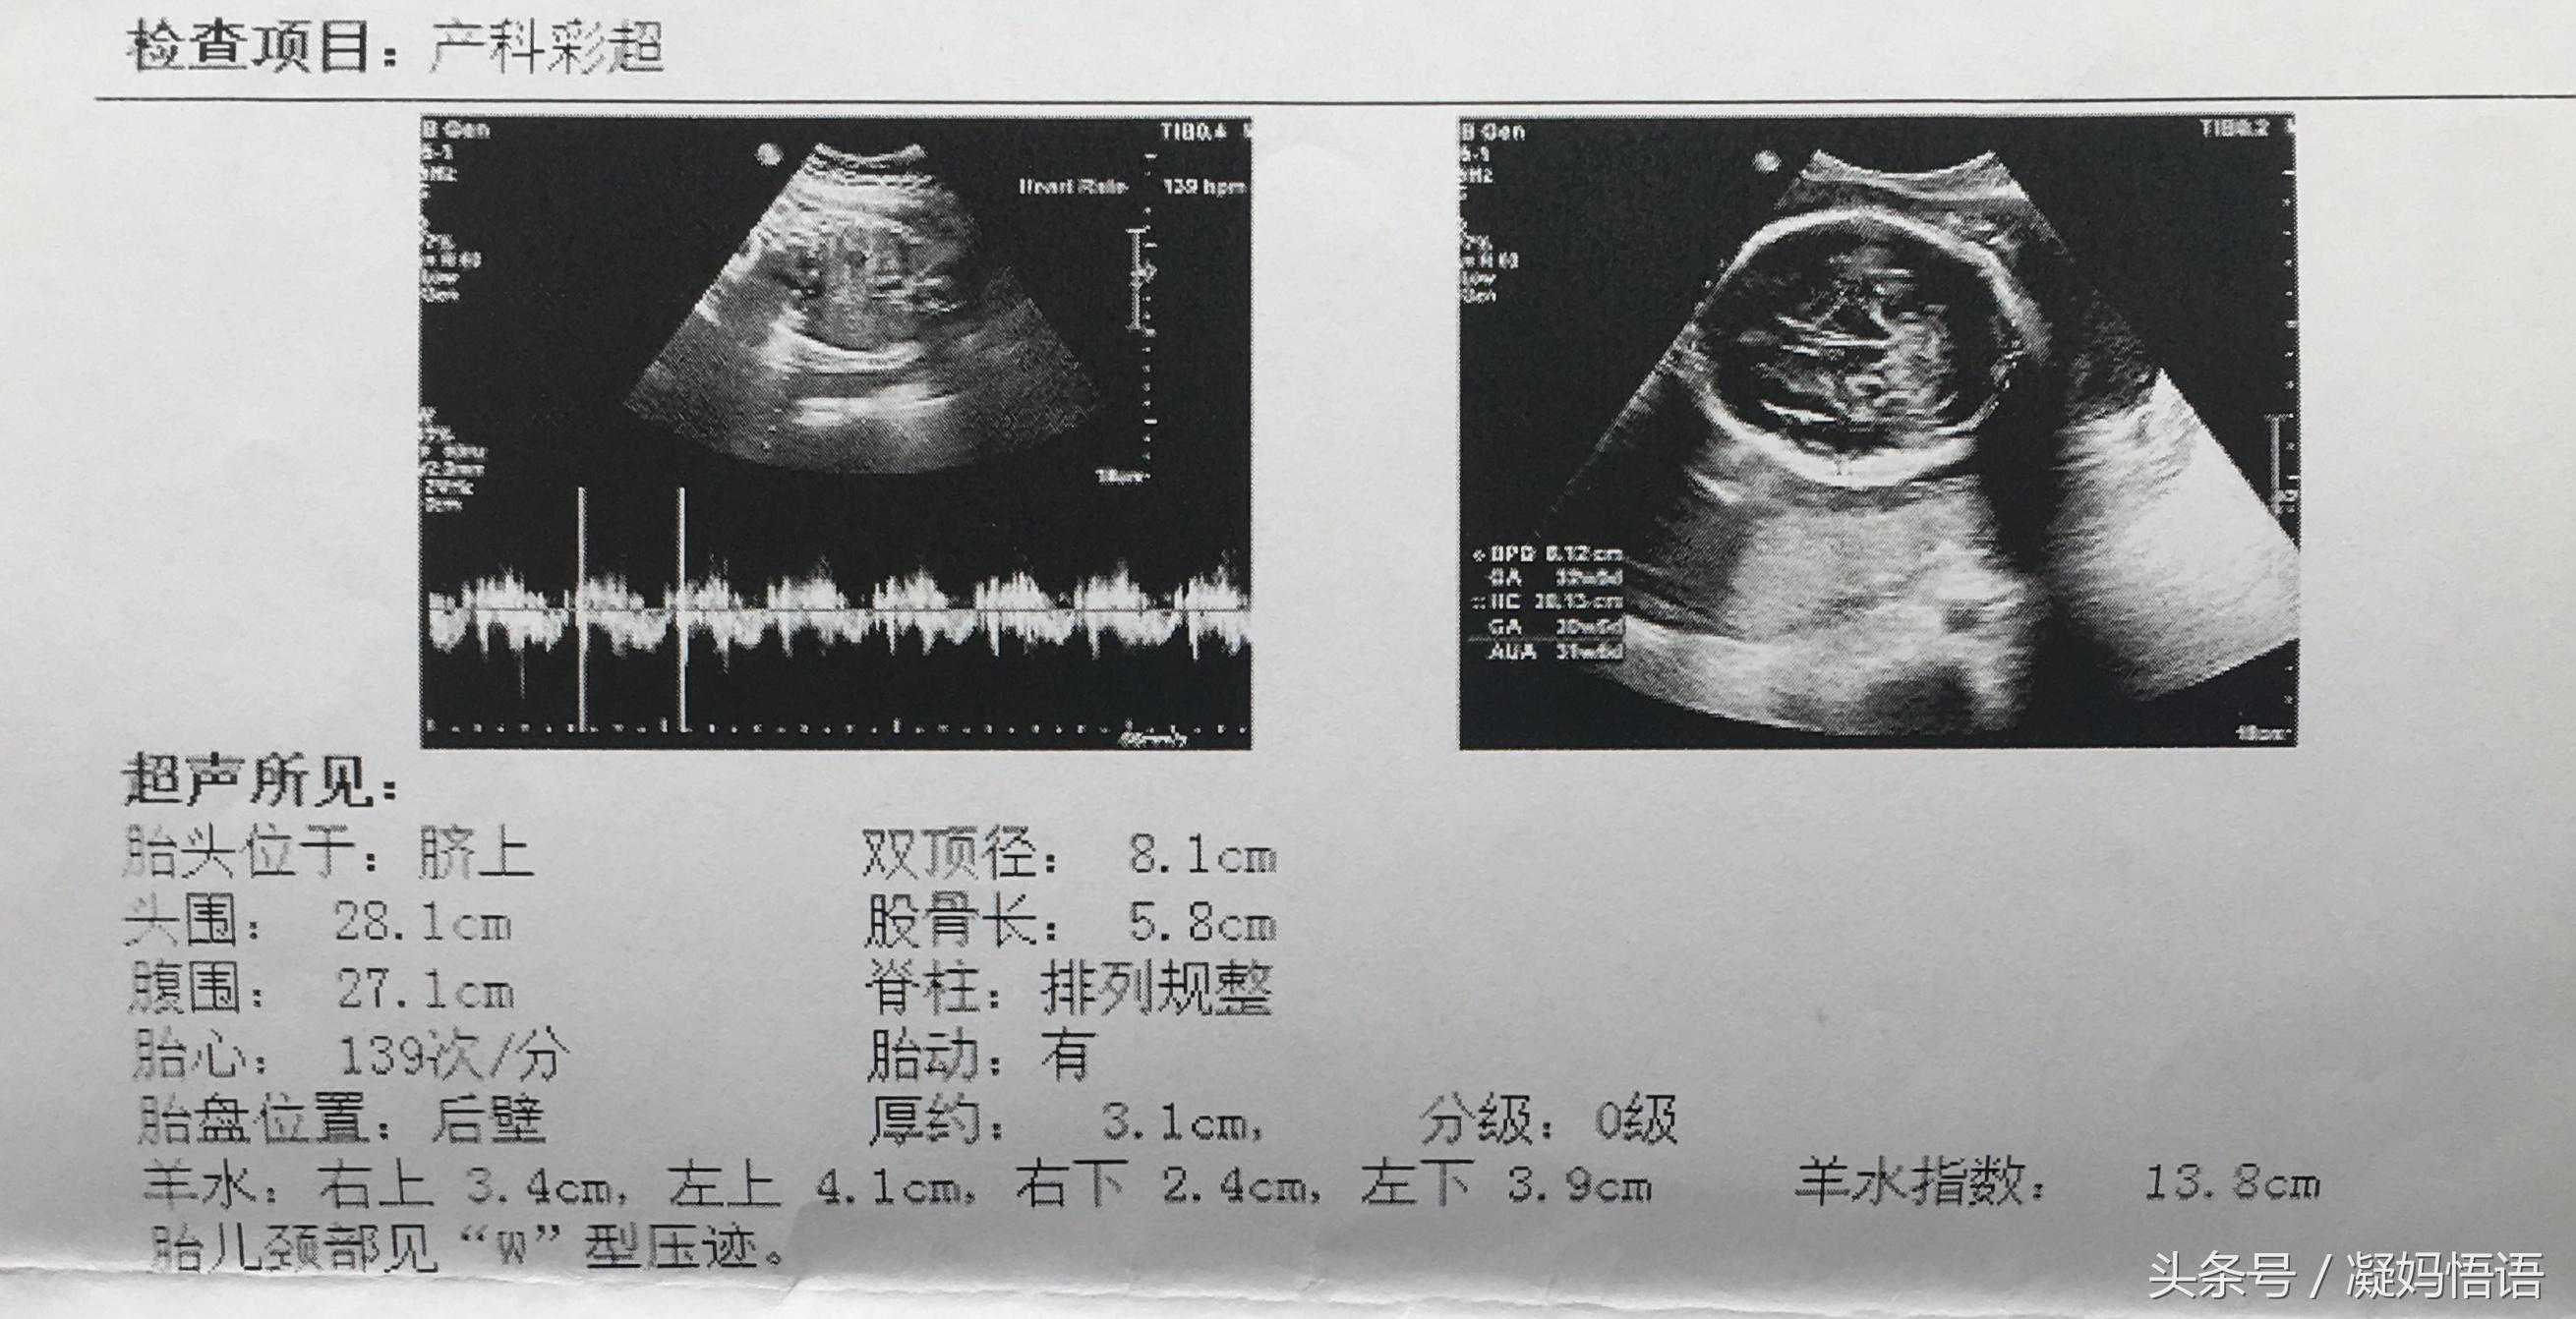

五、第五次彩超是在第32周,例行检查。

胎心率139次,这次小于140了,也是唯一的一次。

双顶径是8.1cm,股骨长是5.8cm,8.1-5.8=2.3,大于2了,或许以此判断是男孩是准的。